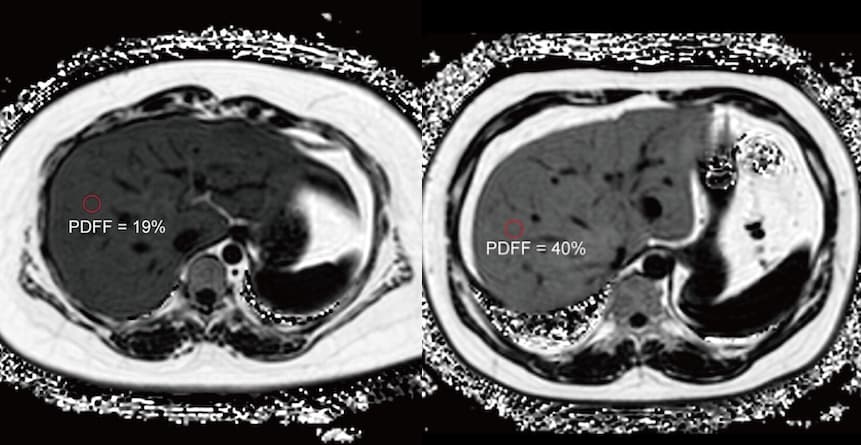

La fraction de densité de proton par IRM est reconnue comme un outil d’évaluation de référence pour quantifier la graisse hépatique. Un travail de recherche publié dans la Revue Radiology évalue la gravité de la stéatose aux moyens de cette pratique. Cet outil IRM est validé par les chercheurs pour prédire le risque de prédiabète et de diabète de type 2 chez les patients obèses.